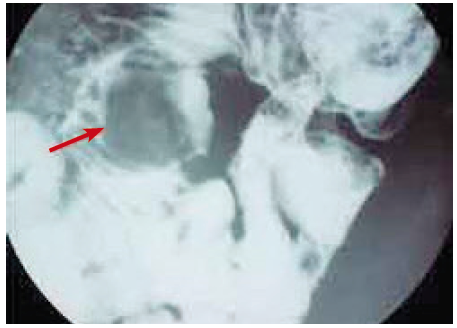

A 44-year old male with history of chronic hypertension presented with 1-month history of nausea, fatigue, and decreased appetite.